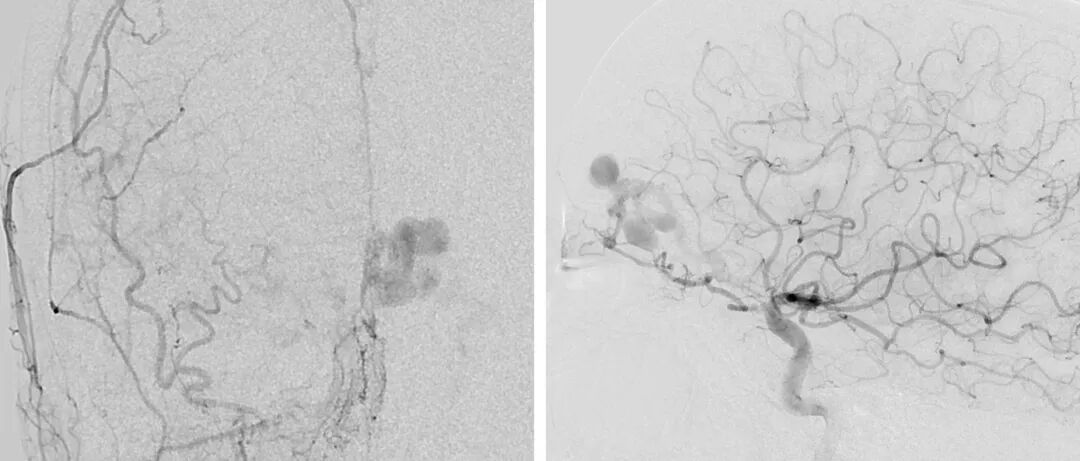

![]()

图2. 左侧颈外动脉前后位血管造影(左)和左侧颈内动脉侧位造影(右)显示一个筛部dAVF,由筛前动脉和镰动脉供血,向皮层静脉引流伴静脉曲张。

筛部瘘位于前颅底,由筛前动脉、眼动脉脑膜支和大脑镰前动脉供血。也可能有脑膜中动脉前支供血。额叶底部、大脑镰的硬膜可与皮层静脉(嗅和额静脉)形成瘘。

曲张的动脉化静脉出血风险很高,可达57%。由于是皮层静脉,不能经静脉途径到达。经动脉途径需通过眼动脉,因此有导致失明的风险。然而,手术治疗不仅简单,而且风险小,将会在幕上动静脉瘘章节描述。